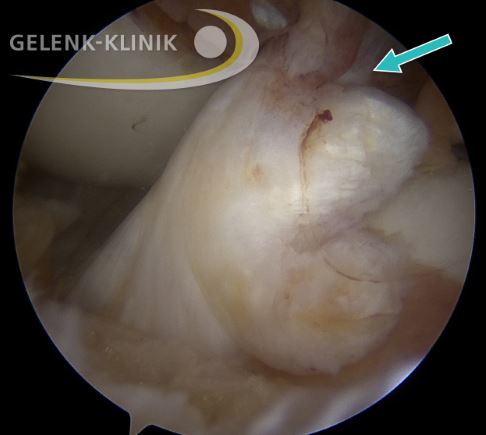

Kreuzbandnaht durch Refixation des gerissenen Kreuzbandes

Bei frischer Diagnosestellung kommt je nach Art des Kreuzbandrisses und der vorhandenen Begleitverletzungen eine Naht des gerissenen Kreuzbandes infrage. Hierzu stehen verschiedene Systeme zur Verfügung. Diese stabilisieren das genähte Kreuzband während der Anheilungsphase. Zunächst muss aber das gerissene Kreuzband wieder genäht (refixiert) werden. Dazu eignen sich besonders knochennahe Ausrisse des vorderen Kreuzbandes. Der gerissene Stumpf wird dabei mit Fäden und Ankermaterialien im Knochen befestigt und kann in den folgenden Wochen und Monaten anheilen. Wenn das gelingt, ist eine Kreuzbandplastik mithilfe körpereigener Sehnen nicht mehr notwendig.

Bevor die Entscheidung für die operative Refixierung des Kreuzbandes getroffen werden kann, ist eine ausführliche MRT-Untersuchung erforderlich. Die Durchführung des Eingriffes ist sehr zeitkritisch: Das gerissene Kreuzband ist nach mehr als drei Wochen nicht mehr so gut regenerationsfähig. Bei der Refixierung ist also eine Operation während der Akutphase innerhalb der ersten drei Wochen nach der Ruptur des Kreuzbandes erforderlich.

Das Implantat aus Polyethylenfäden mit Federsystem können wir nach erfolgreicher Einheilung etwa sechs bis neun Monate nach der Operation in einem kleinen operativen Eingriff wieder entfernen. Bei der Entfernung des Implantates prüfen wir zudem die Heilung des Kreuzbandes noch einmal arthroskopisch.